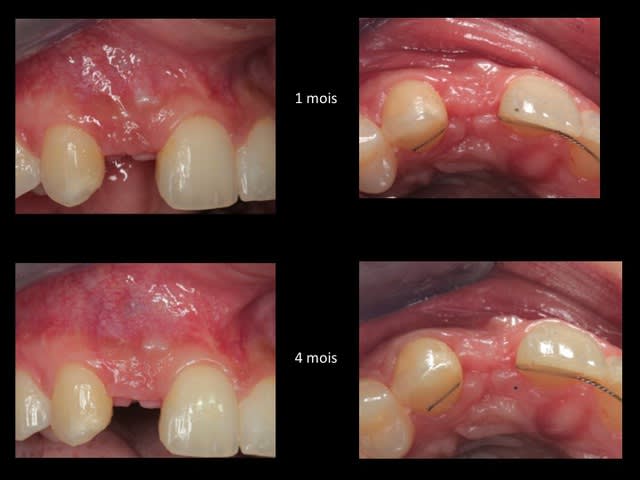

la suite et le début:

scan pré op: pas bcp d'os dispo au niveau de 46 47, y'a fallu aller plus loin derrière

la 11: voir son axe et le peu d'os autour en vestibulaire

photo de la cica à quelque mois

bientôt scan et pose de l'implant